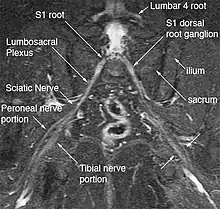

| Deep gluteal space anatomy | |

Anatomy

The hip has five external rotators: The piriformis, superior gemellus, obturator internus, inferior gemellus, and quadratus femoris. The inferior gluteal nerve/artery, sciatic nerve, posterior femoral cutaneous nerve, obturator internus nerve, superior gemellus nerve, quadratus femoris nerve, and inferior gemellus nerves run exit the greater sciatic foramen underneath the piriformis.[6]

Imaging

Magnetic resonance imaging (MRI) and magnetic resonance neurography (MRN) are the diagnostic procedures of choice for deep gluteal syndrome.[4][6][3] MRN provides additional information that MRI alone can't by visualizing structural properties of the sciatic nerve.[3] As an example of the diagnostic improvement of MRN, when MRI is used to assess piriformis muscle asymmetry, it has 46% sensitivity and 66% specificity for piriformis syndrome. When MRN is used and includes unilateral sciatic nerve hyperintensity at the sciatic notch, the sensitivity increases to 64% and the specificity increases to 93%.[3] MRN's advantage is in identifying anatomic nerve abnormalities by visualizing neural structures such as nerve diameter, nerve fascial edema, fascicular appearance, perifascicular and endoneural signal intensity.[5][6] Diffusion tensor imaging / Magnetic resonance tractography is expected to be another powerful clinical tool for diagnosis of deep gluteal syndrome because it can reveal additional physiological information about the nerves, but is still in the research phase.[6]